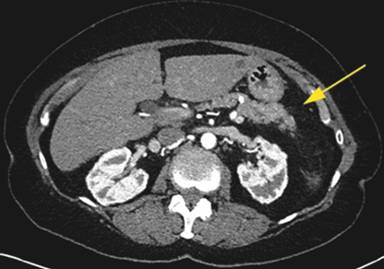

A 64-year-old Caucasian female was referred to our facility for further management of hemorrhagic pancreatitis. The patient had previously presented to an outside hospital with acute onset of severe sharp mid-abdominal pain, back pain, and nausea. She had no prior history of pancreatitis or alcohol use and had a prior cholecystectomy. Initial laboratory tests revealed a normal lipase, calcium, and triglyceride level. She had a history of hypertension, emphysema, depression, and spinal stenosis. She also had breast cancer 13 years prior, which had been treated by lumpectomy, chemotherapy, and radiation. Computed tomography (CT) scan displayed a heterogeneous fluid collection 14.3x11.2x10.0 cm and was interpreted as hemorrhagic pancreatitis involving the body and tail of the pancreas. Before admission to our hospital, she had required intensive care unit support including intravenous antibiotics and a transfusion of one unit packed red blood cells. She was started on total parenteral nutrition and took nothing by mouth. After seven days of support, she continued to have abdominal pain and was referred to our institution. Upon arrival to our facility, the patient was hemodynamically stable and afebrile. A repeat CT of the abdomen with intravenous contrast was performed at our facility 17 days after initial outside presentation (Figure 1), and it demonstrated a heterogeneous fluid collection 9.1x5.8 cm in the anterior pararenal space inferior to pancreatic tail, which likely represented a hematoma. There was also a 6 mm small pseudoaneurysm within the central portion of the fluid collection. There was no evidence of pancreatitis. An angiogram was subsequently performed and demonstrated dilatations and strictures with multiple pseudoaneurysms in the branches of the superior mesenteric artery, inferior mesenteric artery, ileal colic artery, and hepatic arteries, with one being adjacent to the pancreas (Figures 2 and 3). An attempt to embolize the pseudoaneurysm within the hematoma was unsuccessful due to tortuous mesenteric arteries. Other laboratory data obtained included C-reactive protein at 36 mg/L (reference range: 0-8.0 mg/L) and erythrocyte sedimentation rate of 72 mm/h (reference range: 0-29 mm/h). The workup for vasculitis included anti-nuclear antibodies, anti-citrullinated protein antibodies, rheumatoid factor, anti-double stranded DNA antibodies, and complement levels, all of which were within reference limits. Proteinase antibodies and myeloperoxidase antibodies were also negative. Her leukocyte count was not elevated and blood cultures were negative for growth. There was no history of congenital vascular disorders. She had no skin lesions and no renal or neurological abnormalities. A diagnosis of segmental arterial mediolysis was given based on exclusion and imaging. The patient was monitored in the hospital setting for 6 days after transfer and remained hemodynamically stable. Once abdominal pain resolved and the patient was tolerating a regular diet, she was discharged with close follow-up. A CT angiogram conducted four (Figure 4) and eleven months later (Figure 5) revealed resolution of mesenteric pseudoaneurysms and peripancreatic hematoma.

Figure 1. CT abdomen with contrast revealing heterogeneous peripancreatic fluid collection with pseudoaneurysm. |